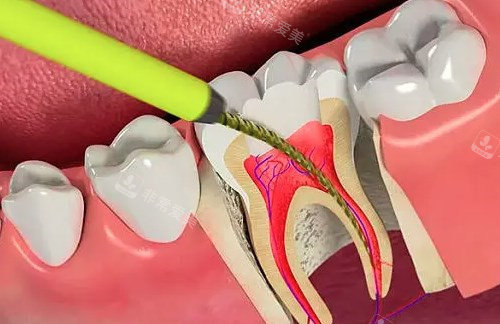

诊疗区域严格按照卫生标准进行设计和布局,每个治疗室都配备了可靠的口腔诊疗设备,如智能化口腔全景机、种植机等。

这些设备不仅能够提高诊断的比较准性和治疗的结果,还能减少患者的痛苦和治疗时间。